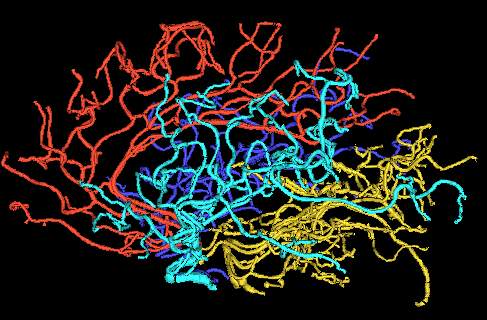

The data are from a Magnetic Resonance Angiography (MRA) study of brain images of a set of human subjects of both sexes, ranging in age from to , which can be found at Handle (2008). A tube tracking algorithm was applied to the MRA images resulting in a segmentation of arteries as shown in the images in Figure 1. See Aylward and Bullitt (2002) and Bullitt et al. (2010) for details of this study.

The artery system feeding the brain can be divided into component systems according to the areas they feed in the brain. In the figure, these systems are colored in gold for the back, cyan for the left, blue for the right and red for the front regions. Each of these regions are studied separately, giving rise to data sets. For each of these regions, the vessel structure is reduced to only its topological (connectivity) aspects by representing it as a simple binary tree. Each vessel tube between two split points is converted into a node in the binary tree, and the two tubes after the split are the children nodes of the first node. Figure 1 gives an example of this conversion. The root node at the top represents the initial fat gold tree trunk shown near the bottom of the figure.

There is one ambiguity in the construction of the representation shown in the right panel in Figure 1. That is the choice, made for each split, of which child branch is put on the left, and which is put on the right. The word correspondence is used to refer to this choice. Throughout this paper we will use the descendant correspondence, where the child with the most number of descendants is assigned to be the left child.